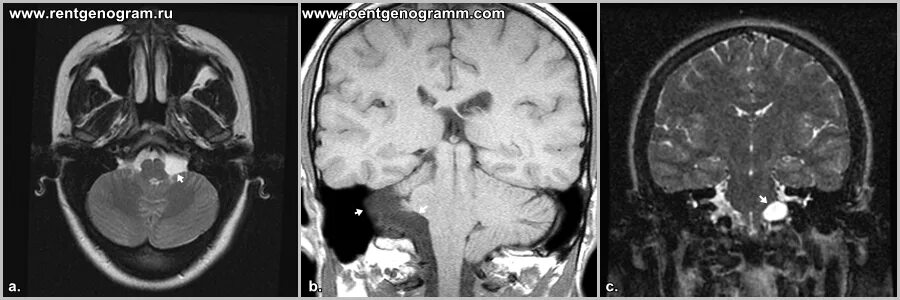

Мрт головного мозга мосто мозжечкового угла